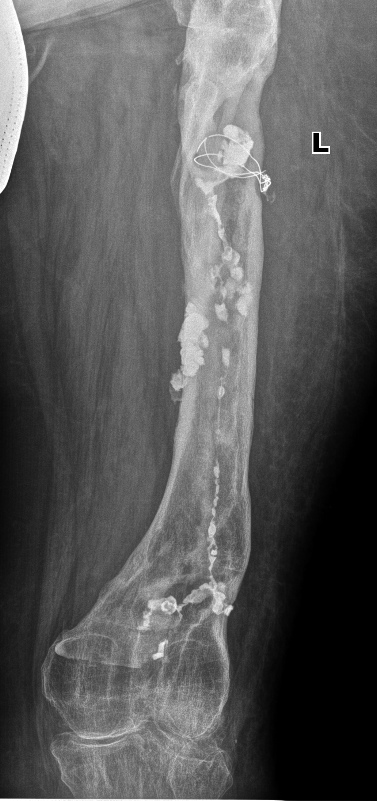

Женщина, 42 года, состояние после перелома левой бедренной кости в верхней и нижней трети, выраженный хронический остеомиелит. В верхней трети диафиза бедренной кости визуализируются остатки проволоки и булавовидной формы инородное тело.

Подозрение на свищ (свищевым ходом (свищем) называется канал, который соединяет место воспаления с какой-либо полостью и создает отток воспалительной жидкости (экссудата) или гноя. Это защитная реакция организма: выведение токсических (отравляющих) продуктов, вырабатываемых микробами).

Выполнена фистулография (методика рентгенологического исследования свищевых ходов с введением контраста) через свищевой ход на передней поверхности нижней трети бедра. Визуализируется свищевой ход, извитой формы. Контрастное вещество распространяется по костно-мозговому каналу бедренной кости от дистального метадиафиза до верхней трети кости (до места установки проволоки) с затеканием в мягкие ткани.

Снимки в прямой и боковой проекциях. Белые штуки вокруг костей - это контраст.